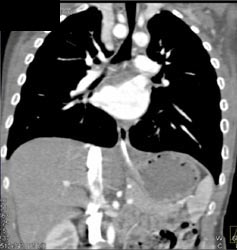

Airway Narrowing Due to Double Arch